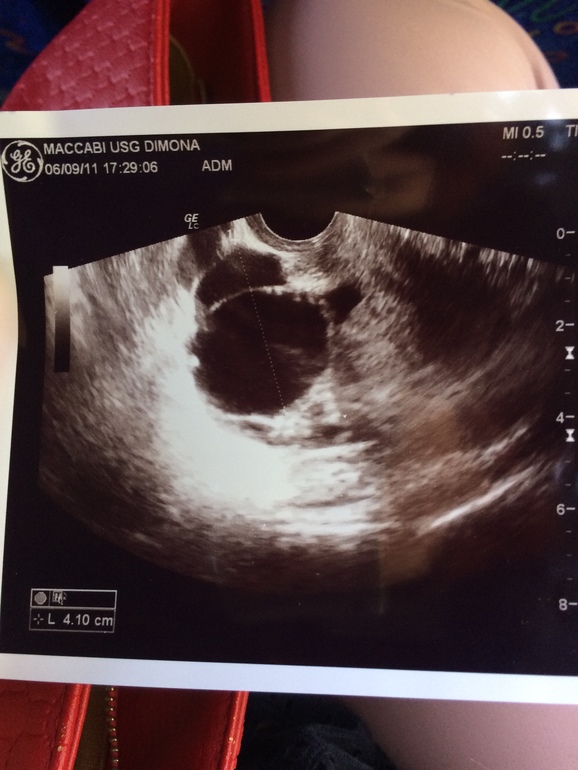

Вышла только что от врача гинеколога , пришла с жалобами на незначительные боли внизу живота и пояснице . Сделала мне ультразвуковую проверку , сказала , что овуляция была это видно по жидкости , хотя по бт овуляции не было та как она 36.5. Увидела кисту в правом яичнике не исключает , что это связанно с беременностью . Назначила проверку ХГЧ через 10 дней , но так же назначила анализы крови на выявление злокачественных процессов . Что мне теперь думать я не знаю ... Так же сказала , что если месячные не придут , то назначает ультразвуковое обследование беременности ...

Прилагаю фото кисты ..

Если фолликулярная киста яичника, то она проходит после медикаментозной терапии. Так что не печальтесь.